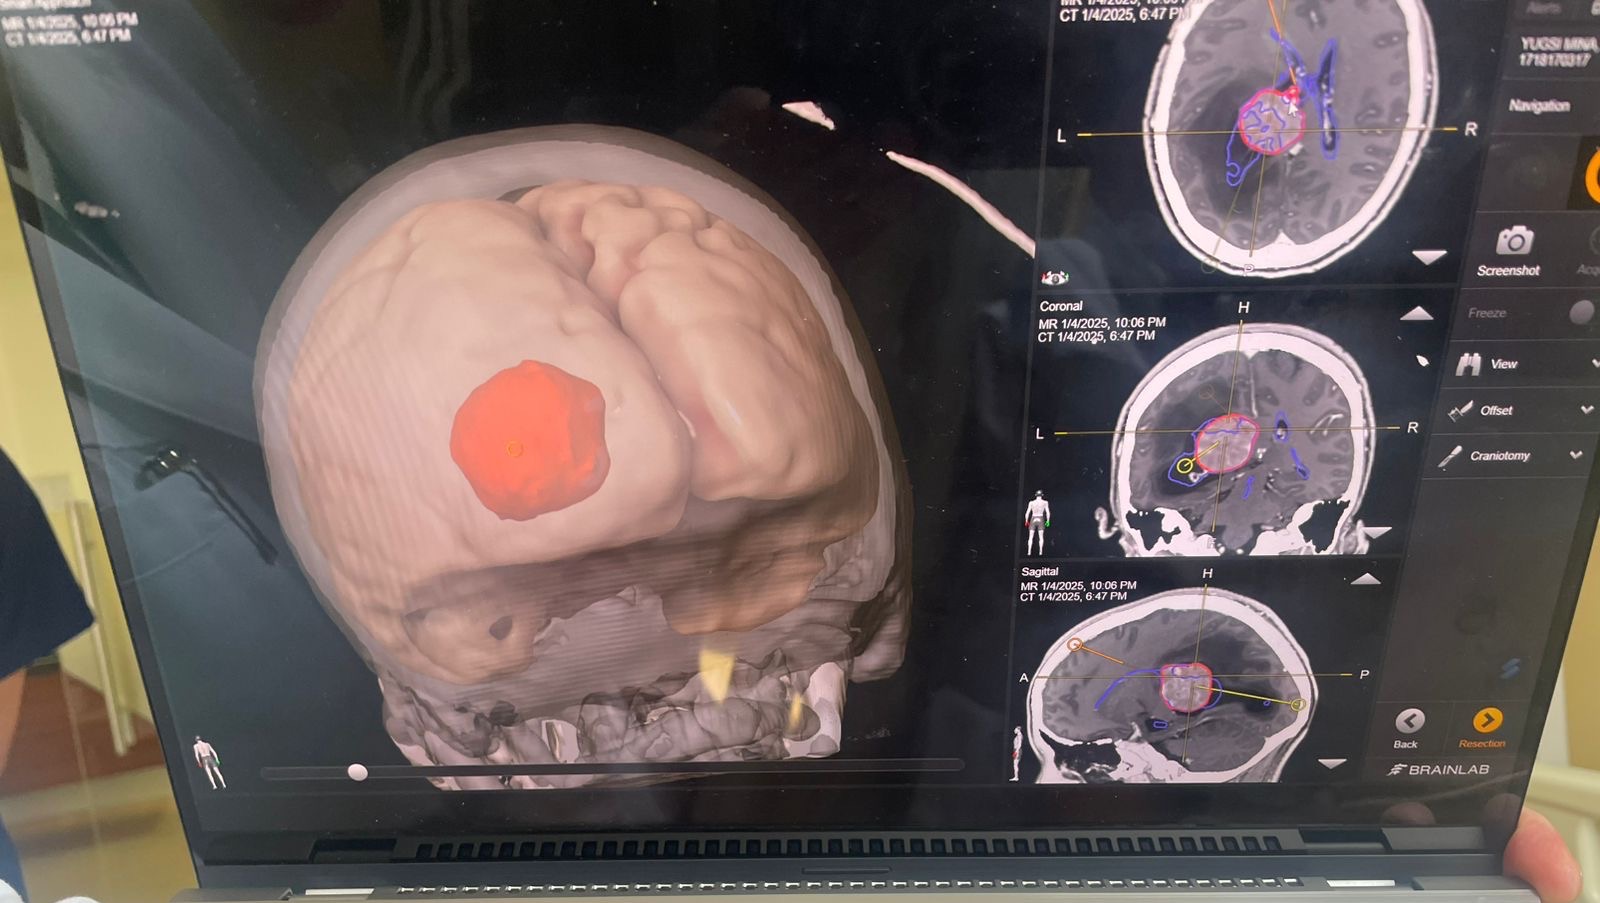

At night I received that call that nobody wants to receive, my mother told me that after medical tests, the result was that she had a very large tumor in the left hemisphere of her brain.

Two days later she had surgery to remove it, the surgery lasted 13 hours.

Por la noche recibí esa llamada que nadie quiere recibir, mi madre me contó que después de los exámenes médicos, el resultado fue que tenía un tumor muy grande en el hemisferio izquierdo de su cerebro. Dos días después la operaron para removerlo, la operación duró 13 horas.